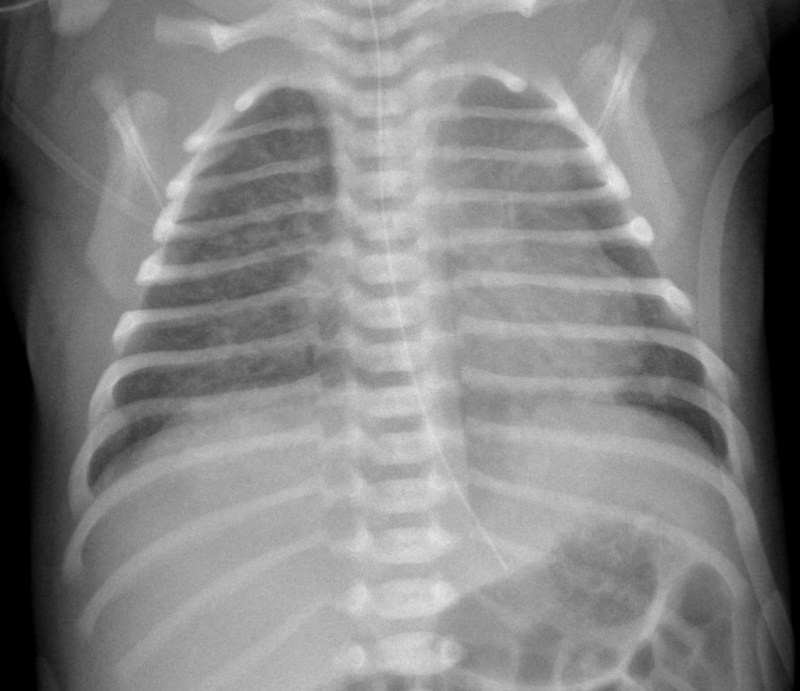

HMD / RDS (Hyaline Membrane Disease / Respiratory Distress Syndrome) Diffuse bilateral granular ("ground-glass") pattern; air bronchograms; low lung volumes Premature infant; surfactant deficiency; improves with surfactant therapy